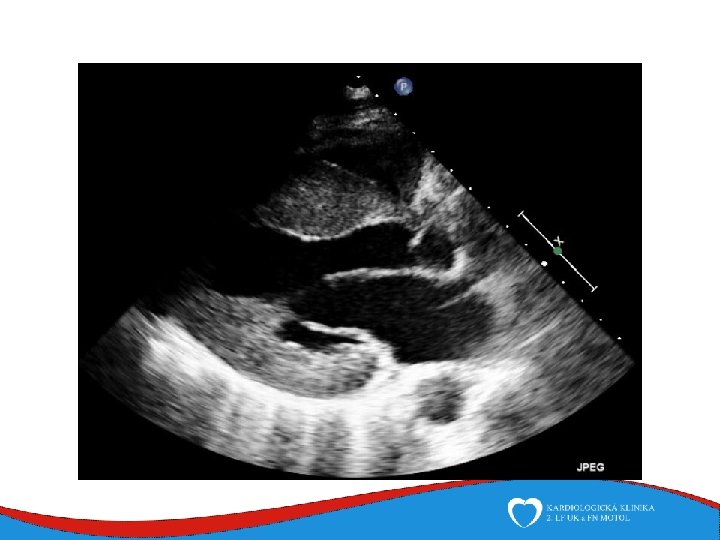

Diagnosis Family history Phisical examination ECG systolic murmur at the apex and lower left sternal border heterogenous LVH, patol. Q , QS, …. ECHO – golden standard MRI septal thickness more than 15 mm, papillary muscles hypertrophy, mitral anterior leaflet elongation, pressure gradient regions of myocarrdial fibrosis regions of late gadolinium enhancement (LGE) Stress test blood pressure responce ECG monitoring ventricular arrhythmia Selective coronarography

ECHO – anterior wall akinesis, LV EF 35%, mild mitral regurgitation, no dilation of right-sided chambers, no pericardial effusion